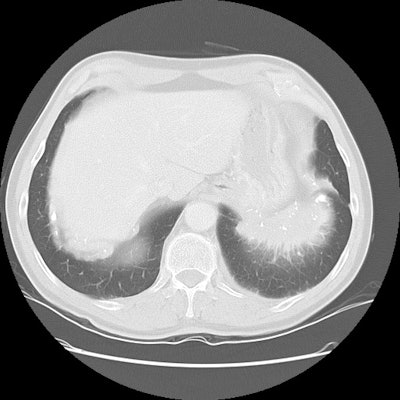

Cryptogenic Organizing Pneumonia (BOOP):

The patient shown below had a long history of inflammatory bowel disease for which she was receiving treatment with sulfasalazine. This agent can result in BOOP.

The CT scan demonstrates subpleural, patchy consolidations with air bronchograms. Patchy areas of ground-glass are also seen. Peribronchial thickening as shown in this case is a common finding.